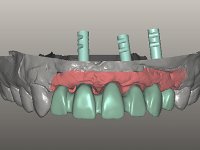

Foi aconselhada a extracção dos dentes 12 e 11 e esperar mais 3 meses para se conseguir uma completa cicatrização da zona. Estabilizada a situação fazer-se –ia um enceramento de diagnóstico que dando origem a uma guia imagiológica permitiria fazer uma TAC. em que o posicionamento idealizado dos dentes pudesse ser relacionado com o património ósseo. O objectivo seria fazer uma ponte cerâmica implanto suportada.

O paciente foi observado conjuntamente e a dúvida que surgiu de imediato foi se seria possível com a regeneração óssea a efectuar poder ser reabilitada naturalmente a zona das papilas interdentárias. Nesse sentido foi feito um enceramento de diagnóstico que contemplaria as duas hipóteses, utilizando ou não a cerâmica gengival. A confecção desse enceramento foi fundamental para expor ao paciente a dificuldade da reabilitação. O wax-up deu origem a um mock-up que foi aprovado pelo paciente e que simultaneamente serviu de guia imagiológica. O caso foi planificado cirurgicamente e realizada uma guia cirúrgica com que foram colocados os implantes. Após 10 semanas foi feita a 1ª impressão para confecção da ponte provisória. Foram criados os primeiros perfis de emergência na gengiva artificial e foi digitalizado o modelo. Por processo de CAD-CAM foi confeccionada uma ponte provisória aparafusada baseada no enceramento de diagnóstico. A ponte trabalhou durante 8 semanas os tecidos moles que foram fielmente copiados numa impressão com técnica de moldeira aberta. Os transferes foram individualizados com resina composta para copiarem fielmente os perfis de emergência criados pela ponte provisória. Confeccionado o modelo de trabalho definitivo, foi realizada uma infra-estrutura em zircónio seguindo a orientação do enceramento de diagnóstico. O assentamento da infra-estrutura foi testado em boca e simultaneamente foi novamente impressionados os tecidos moles com um silicone fluido. Nessa consulta foi feito o levantamento da cor. Os dentes 13 e 23 apresentavam uma saturação anormalmente forte que resolvemos não valorizar, optando por privilegiar a relação com o sector antero-inferior. Foi realizada uma nova gengiva artificial com a impressão que acompanhou a impressão de arrasto com a infra-estrutura. Após a colocação da cerâmica na infra-estrutura foram coladas as meso-estruturas. O trabalho final foi aparafusado lentamente permitindo a adaptação dos tecidos moles.